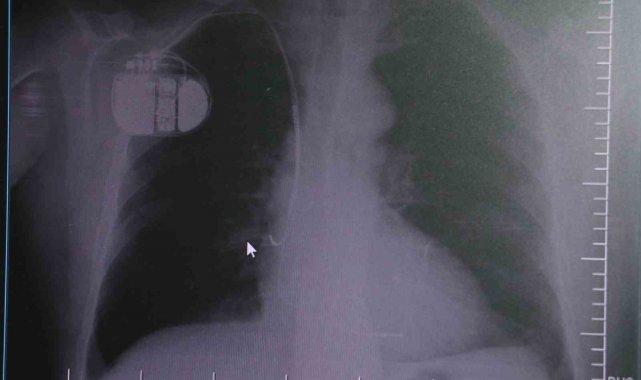

Konuya ilişkin açıklamalarda bulunan Sivas Medicana Hastanesi Kardiyoloji Bölümü Uzmanı Dr. İsmail Erdoğu, kalp pilinin önemine vurgu yaptı. Erdoğu, Yeni nesil kalp pillerinin MR cihazlarına girmeye imkan sağladığı, ancak tarama cihazlarından geçmenin önerilmediğini ifade ederek, "Soğuk hava nedeniyle oluşan titremeler, kalp pilinin kalbin durduğunu sanmasına ve yanlış şoklamaya yol açabilir. Bu nedenle hastalarımızın bu dönemlerde daha dikkatli olmalarını öneriyoruz" dedi.

Kalp pilleri ile MR cihazına girilebileceğini belirten Erdoğu, "Çok büyük bir ameliyat değil ama yine de ciddi bir cerrahi işlem. Kalp pili, tıpta son 30 yılda yaşanan gelişmelerden en büyüğü. Bir bilgisayarın küçültülüp insan vücuduna konulmuş hali aslında. İnsan ömrünü ciddi oranda uzatan bir tedavi. İnsanlar bir şokla hayata tutunurken, pil olmasaydı öleceğini düşündüğümüz birçok hastamız var. Kalp pilinin bu özelliği, uygun hastalarda ciddi oranda ani ölümü engelliyor. Hastanın başına gelecek bir kalp durması durumunda yanında bir sağlıkçı yoksa, onun ritmini düzeltecek defibrilatör cihazı yoksa hastayı hayatta tutmak mümkün değil. Uygun endikasyonlarda kalp pili olduğu zaman, pil hastaların ritmini algılıyor ve acilde yapılan şoklamayı yaparak hastayı hayata döndürüyor. Kalp pillerinde yeni teknolojilerle MR'a girmek mümkün, tomografiye zaten girebiliyorlar. Tarama cihazlarından geçmelerini uygun görmüyoruz. Bu tarz durumlarda hastalarımız 'kalp pilim var' dediğinde muaf tutuluyorlar. Kalp pilleri ciddi teknolojik cihazlardır. Vücudun içindeki titreşimi, örneğin mikser kullanmak, kolunu sallayacak herhangi bir eylem kalp pilinde olumsuz etki oluşturabilir. Soğuk havalarda vücutta oluşan ciddi titremeler kalp pilinin hafızasını karıştırıp kalbin durduğunu düşündürebilir ve gereksiz şoklama yapabilir. Bu tarz kişilerin soğuk havalarda daha temkinli olması gerekir" diye konuştu.